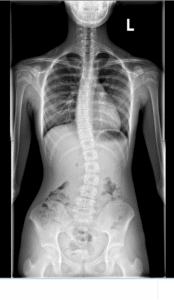

♦wykonanie zdjęcie RTG w płaszczyźnie czołowej ( AP) w przypadku wątpliwości lub w celu potwierdzenia diagnozy. Skrzywienie powyżej 10 st. w skali Cobba określamy skoliozą.